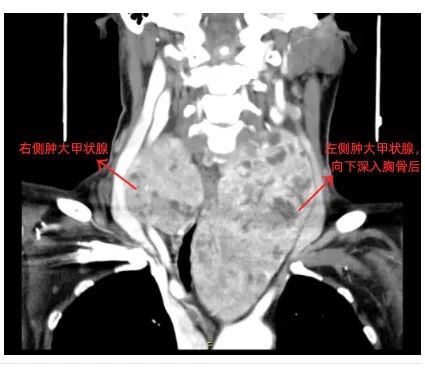

外院CT提示:

胸骨后甲状腺肿,气管压迫明显

术中见双侧甲状腺腺叶非常肿大

左侧腺叶约16cm*8cm

右侧腺叶约8cm*6cm

周围血管丰富

左侧甲状腺最下缘深达主动脉弓水平下缘